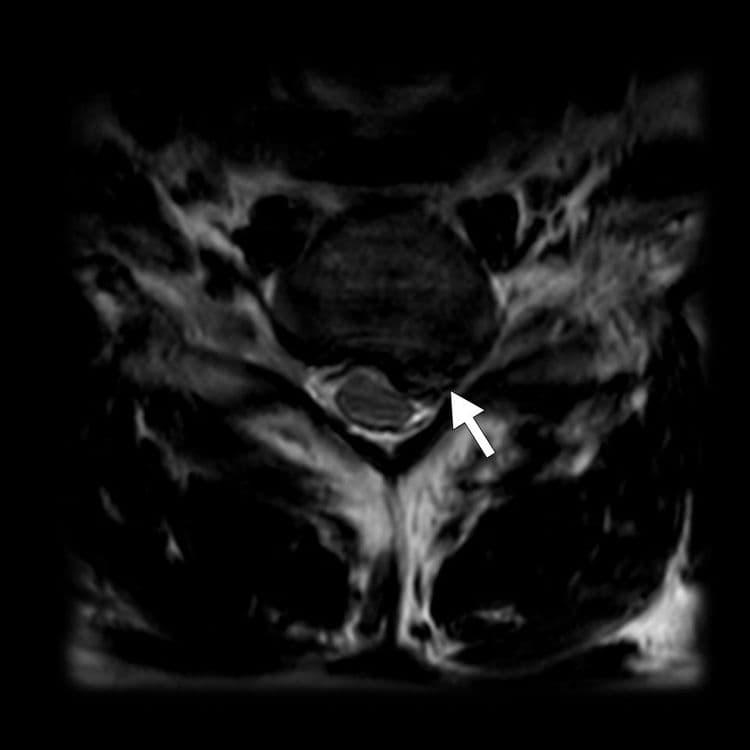

Lyse isthmique du rachis lombaire chez une adolescente pratiquant la natation

MRI